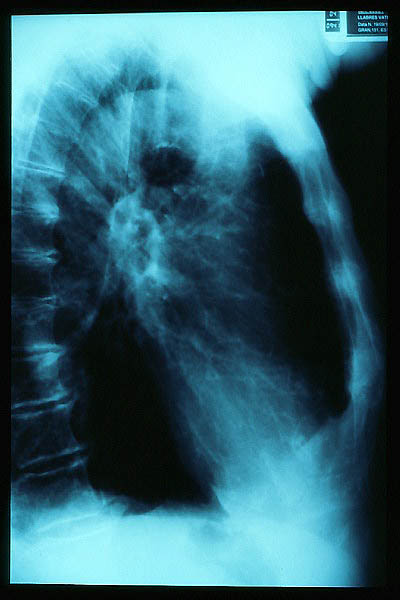

Fibrosis pulmonar. ICC.